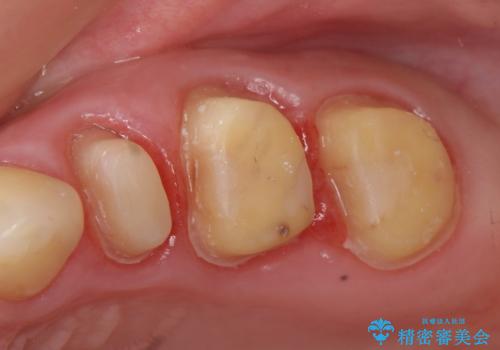

- 他院にて左上5番目の歯の根管治療を行っていたが、痛みが引かないため当院にいらっしゃった方の症例です。

左上5は再根管治療を行い症状の緩解を確認後、オールセラミッククラウンによる補綴を行いました。

左上6、7番目の歯もしみるとのことだったので古い樹脂及び虫歯を除去後、オールセラミッククラウンによる補綴を行いました。

※右上5は歯肉縁下まで虫歯だったため歯冠長延長術を提案しましたが希望されませんでした。